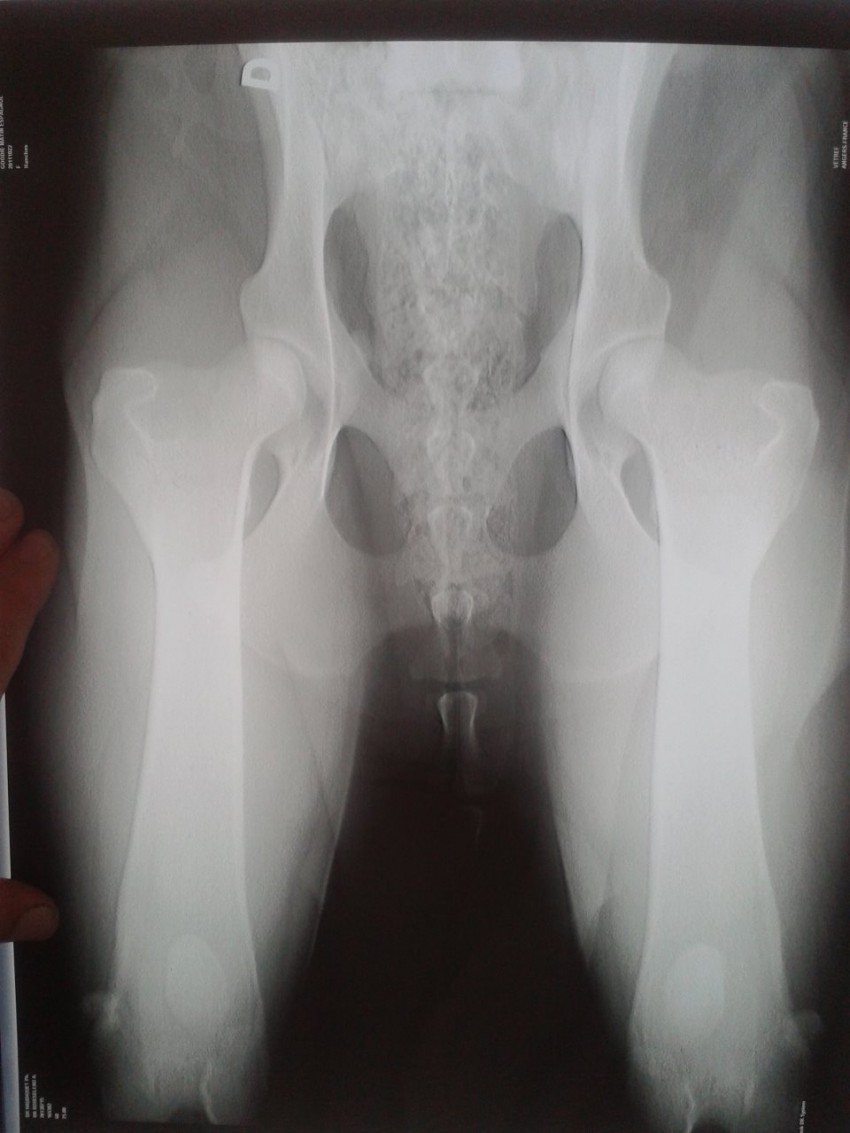

indemme du gène fibrilinne2 (AA) officiellement indemme de dysplasie

radio A/A